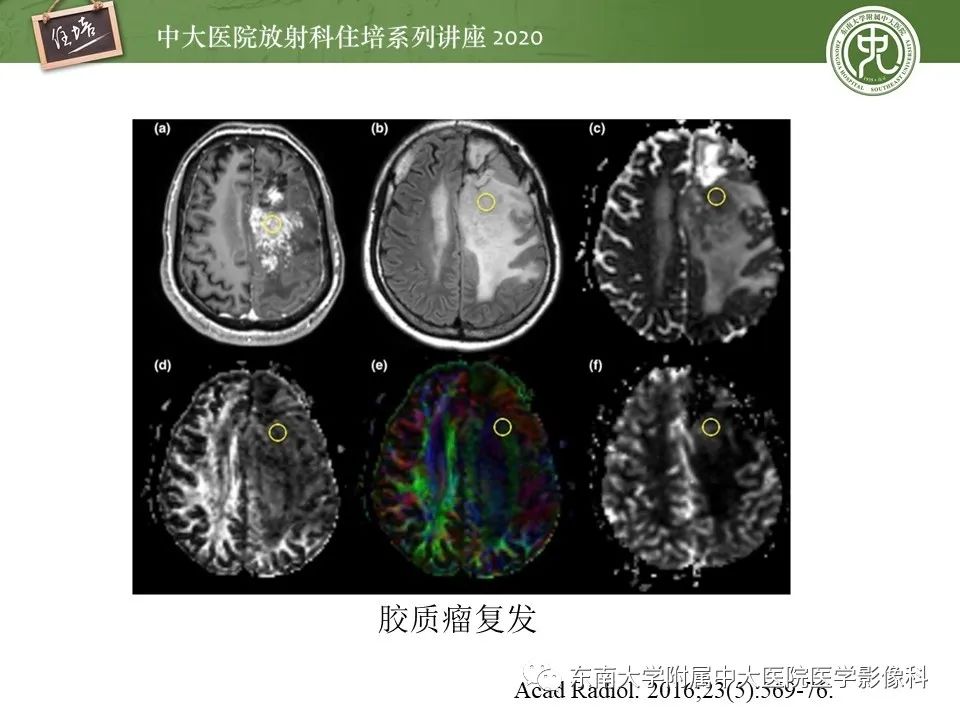

胶质瘤复发与放射性脑损伤MR鉴别